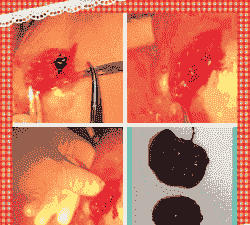

对于内部毛细血管破裂造成的出血,可以肌注止血敏,若止血效果不佳,则需采用局部按压止血。在伤口处用纱布攒上肾上腺素按压,并进行清洗复位缝合,同时进行消炎处理。一般打两天消炎针即可自行恢复。

使用温高锰酸钾溶液清洗消毒外阴部,以减少感染的风险。

对于严重的炎症,可以局部使用抗生素或消炎药物,如鱼腥草注射液和头孢噻呋钠,每天一次,连用三天。